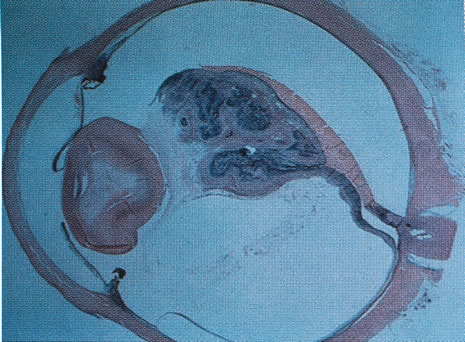

Newborn males often present with a vascularized retrolental mass consisting of hemorrhagic vascular and glial tissue (Fig. 6). Arrest in embryonic retinal development during the third to fourth month of gestation has been proposed as a cause of ND.101 Supporting this hypothesis, histopathologic studies revealed neuroblastic inner and outer layers containing rod and cone precursors but complete absence of retinal blood vessels in ND102 (Fig. 7). The vascular nature of the retrolental mass has led others to hypothesize that a primary defect in vascular proliferation causes ND.103 The initial avascular retina could lead to neovascularization that results in the retrolental mass.

Fig. 6. Norrie's disease. A dense, white retrolental mass is present on gross evaluation of the enucleated eye. (Courtesy of J. D. M. Gass, M.D.)10

Fig. 7. Histopathologic section in Norrie's disease. Section shows retinal detachment and some rosettes of immature retinal cells within the hyperplastic vitreous. (Courtesy of J. D. M. Gass, M.D.)10